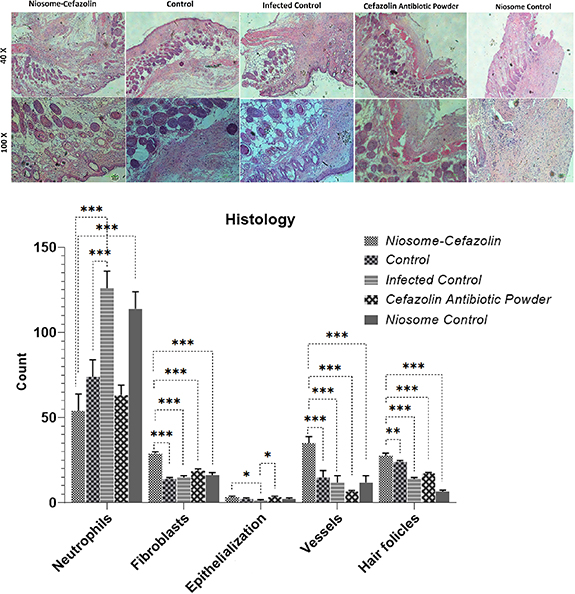

2.4.8. Histopathology in vivo studies

Histopathology experiments were carried out to evaluate the effects of cefazolin and cefazolin-loaded niosome against MRSA biofilm‐mediated infections. A 5 mm full-thickness excision wound healing model [36] was created using a 5 mm biopsy punch in the dorsal skin of BALB/c mice. Polycaprolactone (PCL) scaffold provided by Fanavaran Nano-Meghyas Corporation (Fnm co. Ltd.) was punched with a 5 mm biopsy punch sterilized by UV radiation. The PCL pieces were put on the bottom of a sterilized petri dish and 20 ml of BHI broth inoculated with MRSA was poured on them and incubated for 24 h at 37. The mice were anesthetized with an appropriate amount of ketamine/xylazine based on their body mass following shaving their dorsal hair. A silicone ring (15 mm outer diameter and 6 mm inner diameter) covered around the wound by suturing to the dermis of the BALB/c mice. Then, biofilm-containing PCL pieces and wounds were placed in mice for 3 h except for the control group. Afterward, the nano-fibrous mats containing biofilms were removed and the wounds were treated by 3 ml of lyophilized cefazolin-containing niosomes, niosomes, and 3 M TegadermTM containing cefazolin except for the control group. Each group was kept in their post-operation cage on a 12 h light/dark cycle with access to food and tap water and libitum and received human care. On 21st day post-operation, the healed area on the dermis was removed and kept in a 10% formalin solution for further pathology investigations. Hematoxylin and eosin (H&E) staining were performed and the neutrophils, fibroblasts, epithelium layers, and vessels were counted to evaluate the healing progress. Ethical approval for this study was obtained from the Pasteur Institute of Iran (IR.PII.REC.1398.025).

Standard image High-resolution image3.8. Histopathology and in vivo results

Macroscopic monitoring of skins was conducted by the 21st day in all five groups (figure 8). The healing signs including wound closure and hair formation observed in wounds treated by niosomal cefazolin healed similar to non-bacterial contaminated wounds. Infected wounds treated by empty niosomes and non-treated bacterial contaminated wounds did not close properly and hair formation had not been observed.

Standard image High-resolution imageH & E staining was conducted on the 21st day-old model wounds (see figure 9). Histological experiments demonstrated high counts of neutrophils in niosome control and infected control groups. The fewest neutrophil count was observed in niosomal cefazolin treated group. The highest number of hair follicles (HF), fibroblasts, and vessels as well as the level of epithelialization was observed in wounds treated by niosomal cefazolin (figure 9).

Figure 9. Histopathology results of wound infection and H&E staining of wound tissues in Cefazolin-loaded niosomes, Cefazolin powder, non-loaded niosomes, and bacterial contaminated and non-bacterial contaminated control wounds. The wound treated with cefazolin-loaded niosomes had the lowest count of neutrophils and the highest number of HF, fibroblasts, levels of epithelialization and angiogenesis.

Histopathological experiments were conducted to evaluate wound healing and tissue regeneration properties of cefazolin-leaded niosomes. In our study, nanofiber scaffolds were used as a surface-borne model biofilm. These nanofibers mimic the natural fibrous extracellular matrix of skin tissue, allow gas circulation, exudate absorption, and prevent microbial contamination [44]. Furthermore, they can be loaded with various biomolecules including antibacterial peptides, hormones, cytokines, etc. PCL fibers were used as our scaffold due to high permeability to a wide range of drugs and appropriate biocompatibility and considered a suitable candidate for controlled drug delivery [45, 46]. Macroscopic results of in vivo and in vitro examinations on our wound-model biofilm showed no bacterial contamination on the day 5th post wound infection. The results of H&E staining showed a significant increase in counts of healing factors including fibroblasts, neutrophils, and HF as well as the level of angiogenesis. The number of neutrophils as an inflammation index was approximately half to that of infected control. It seems that cefazolin-loaded niosomes successfully reduces inflammations in the site of infection and concurrently improved healing signs compared to free antibiotics and facilitated wound healing.